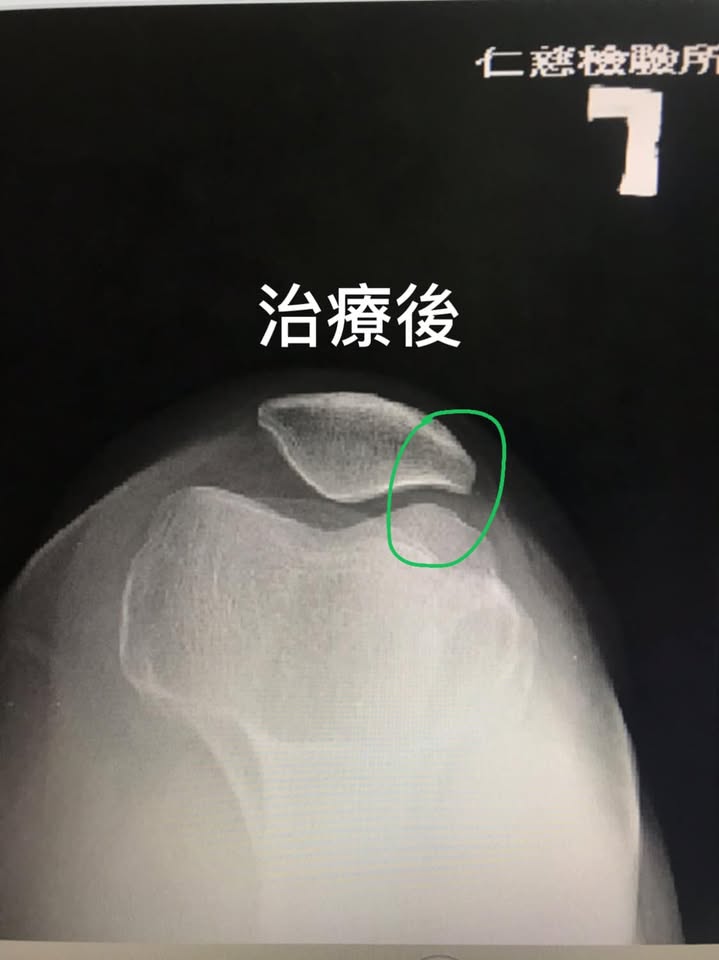

「髕骨外翻」矯正前後對比影像

我們非常的開心且訝異,在第二次的治療就感覺膝蓋輕鬆不少,而在八周的治療後,右側膝關節間隙明顯打開,而且原本左側臏骨外翻也改善不少,當然患者臨床症狀大幅度消失,這只是個案報導,並非每個人都有同樣效果,囑咐游大姊還是要常訓練股四頭肌跟避免久蹲久站等會傷害膝關節的動作

🆘臏骨外翻怎們用超微針刀處理:

從外側筋膜卡壓最緊的地方下針,從髂脛束一直到股骨大轉子甚至是臀中肌的筋膜都要徹底鬆動